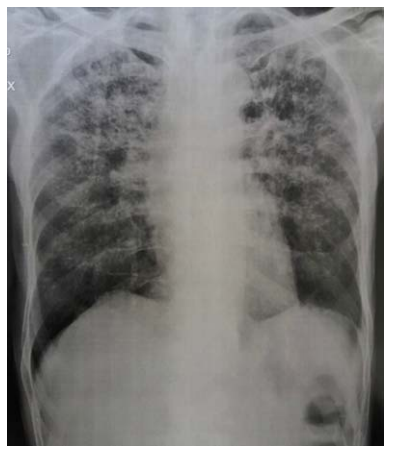

Es solicitada tomografía de tórax urgente que evidencia múltiples áreas de consolidación alveolar en paréquima pulmonar bilateralmente, con predominio central y asociado a bronquiectasias y bronquioloectasias con focos de cavitación (tb/paracoccidioimicose).

Se inicia tratamiento con trimetroprin-sulfametoxazol. Después de 8 días mejora el cuadro respiratorio y es egresado con trimetroprin- sulfametoxazol oral 480 mg 2 comprimidos cada 12 horas y dexametasona 4 mg cada 6 horas. Se toma muestra de suero para serología Blastomicosis-anticuerpos paracoccidioidomicosis con resultado no reactivo y se realiza otra radiografía de tórax (Figura 2).

Es solicitada broncoscopia (que es realizada un mes después) con toma de muestra para estudio (lavado bronquial) siendo los resultados para pesquisa microscópica de Bacilo Acido-Alcohol Resistente (BAAR) con coloración de Ziehl-Neelsen negativo, Micológico directo negativo y toma de biopsia transbrónquica negativo para células atípicas y es confirmado el diagnóstico de Paracoccidioimicosis. Se inicia tratamiento con itraconazol 400 mg por día y continúa con trimetroprin-sulfametoxazol. Actualmente evoluciona satisfactoriamente con mejoría clínica evidente.